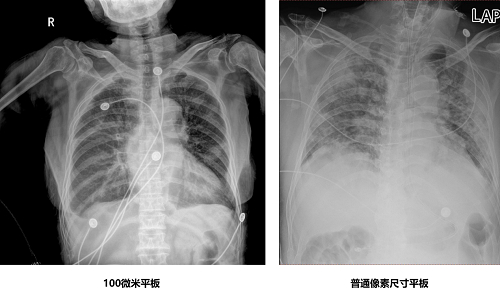

首先,来比较一下两款设备的图像效果。两款移动DR均搭载了100微米探测器,均采用了17*17英寸的大尺寸平板探测器,空间分辨率均达到5线对,像素均为1800万。在近两千万像素的加持之下,两款百微移动DR都能够获得更加高清、低剂量的图像。基于百微平板的高清成像,可以灵活应用于新冠疫情救治下隔离区大量患者的多次肺部影像检查,快速进行肺部影像拍摄以监测病情变化,其高清成像对于肺部症状的细节成像更加精准。此外,两款百微平板移动DR设备均可灵活配备10x12、14x17等各种尺寸高清探测平板,满足疫情防控下急诊、ICU等临床对于胸部影像诊断的需求,此外对于NICU、手术室、门诊、骨科、疼痛科等各个临床场景百微移动DR也大有可为。

百微移动平板的高清成像功能在新冠疫情的诊治中,价值显著。根据奋战在抗疫前线的影像领域专家经验,更为高效的X光机设备对于确诊后的患者病情监测以及大量的治疗随访应用价值非常大。基于百微平板可以灵活应用于隔离区大量患者的多次肺部影像检查,快速进行肺部影像拍摄以监测病情变化,高清成像对于肺部症状的细节成像更加精准;同时,图像可随时进行无线传输,便于临床诊断和会诊。